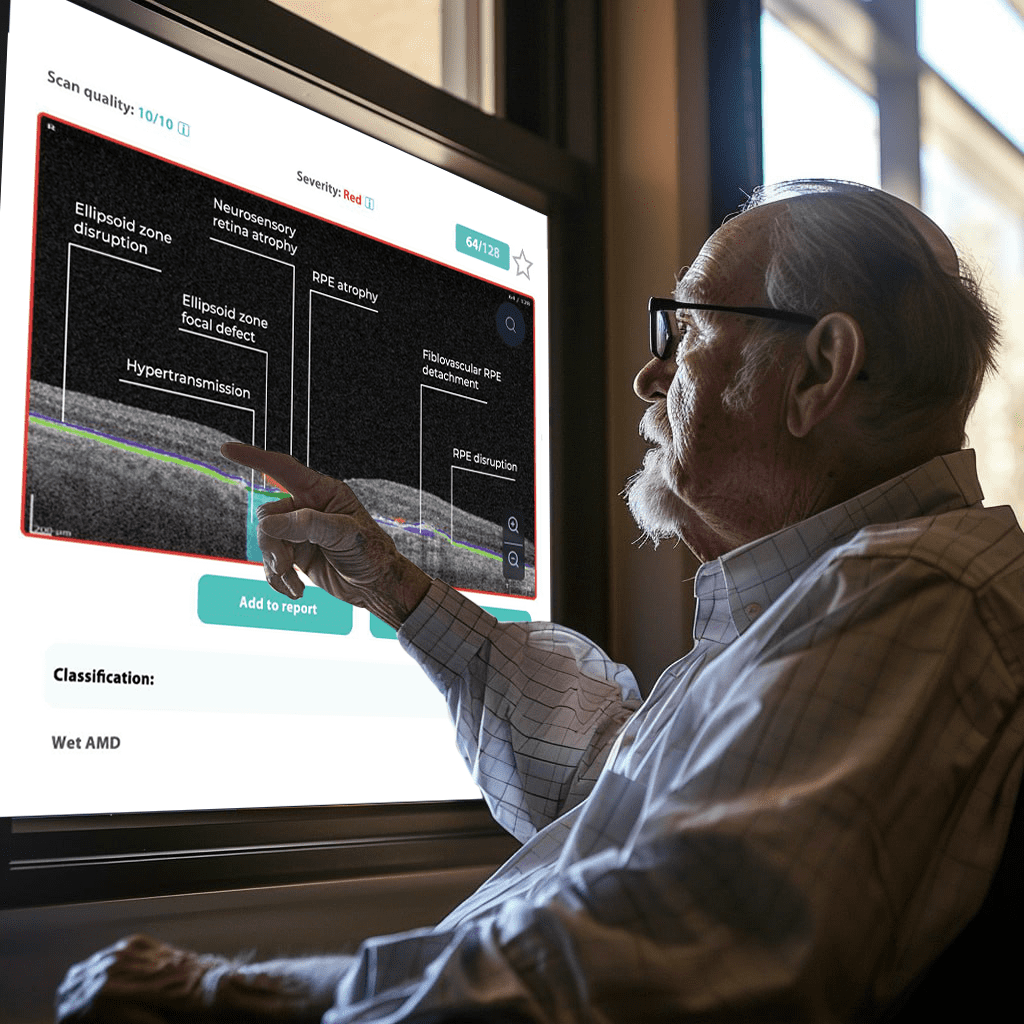

Dr. Maria Sampalis, OD, the owner of Sampalis Eye Care, Rhode Island, utilizes two such programs in her practice. To support her specialization in dry eye management, she employs CSI Dry Eye. Additionally, she uses Altris AI, an AI-powered platform for OCT scan analysis, to provide a second opinion and enhance diagnostic accuracy.

Dr. Sampalis finds that the Dry Eye software allows her and her staff to analyze symptoms and images comprehensively, improving patient care, time savings, and increasing diagnostic precision. See how OCT AI works here.

Her patients also appreciate Altris AI, which analyzes OCT scans for over 70 pathologies and biomarkers while also calculating the risk of developing glaucoma.

Working with specialized software solutions improves diagnostic accuracy and aids in patient education. Visual representations of their conditions, facilitated by these technologies, empower patients with a clearer understanding, leading to increased treatment compliance.

Eye Place, an optometry center in Columbia, also leverages Altris AI, among other cutting-edge technologies. They capture images using the Topcon Maestro2 OCT and use Image Net6 software to export DICOM files to the Altris AI platform.

The most immediate and practical AI implementation in optometry is the analysis of medical images, such as fundus photos and OCT scans.

They require no additional equipment beyond the OCT and fundus cameras many practitioners already own, are cost-effective, and add huge value to a practice.

For instance, AI today can assess the early risk of glaucoma based on the GCC asymmetry measurements. Here is how AI-powered OCT workflow would look.

AI-assisted readings of OCT scans are already helping not only with pathology detection but also with the analysis of its progression or response to treatment. This represents a new approach to monitoring, where practitioners no longer need to sift through various patient notes but can directly compare reports from previous examinations and observe how, for instance, shadowing has changed in micrometers.